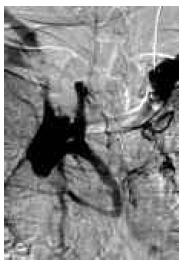

The patient was a 46-year-old West Indian man with a history of severe peripheral vascular disease who had presented initially 7 years earlier with accelerated hypertension and end-stage renal failure. At that time, he was started on temporary-line hemodialysis, followed by formation of a left brachio-cephalic fistula. The fistula failed because of a spontaneous thrombosis 4 years after its creation. Central venous mapping revealed bilateral brachiocephalic vein occlusions and no flow in the superior vena cava (Figure 1A and 1B). The central venous occlusions were considered unsuitable for endovascular recanalization, and the patient was started on peritoneal dialysis.

Figure 1A. Right subclavian vein occlusion, with no flow evident in the right brachiocephalic vein or the superior vena cava.

Figure 1B. Left brachiocephalic and superior vena cava occlusions.